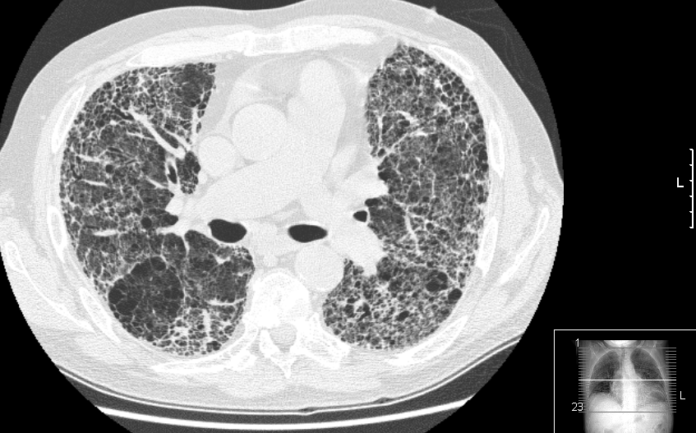

El diagnóstico de la FPI requiere una evaluación exhaustiva. Tras la auscultación, donde se pueden detectar crepitantes secos, conocidos como sonidos de “velcro”, es necesario realizar una tomografía de alta resolución del tórax, que proporciona una imagen detallada de los pulmones. También se recomienda llevar a cabo pruebas de función pulmonar para evaluar la capacidad respiratoria y determinar la evolución de la enfermedad.